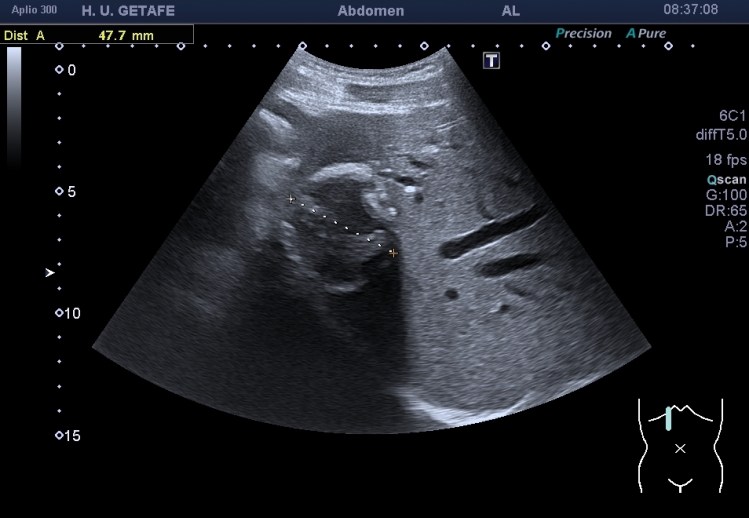

Durante la exploración de una eco de abdomen en el contexto de un paciente que acude por elevación de transaminasas observo una imagen heterogénea, irregular, con una pared marcadamente calcificada, bilobulada de gran tamaño que medí en dos partes ya que me pareció claramente que estaban diferenciadas.

Una de ellas, la primera, era mucho más hiperecogénica y más pequeña, su centro estaba mas calcificado, su sombra acústica posterior era mucho más acuciada y llamaba más la atención. Justo al lado, otra lesión de mayor tamaño, su calcificación era mucho más sutil y más periférica delimitando una LOE hipoecogénica de un tamaño muy importante, adyacente a la más pequeña, como he comentado previamente. Ambas sin señal Doppler.